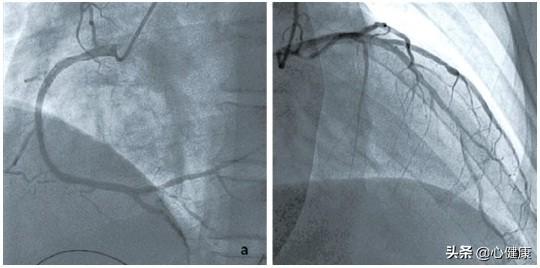

この問題を理解する前に、心血管系の狭窄がどのようにして起こるのかを理解する必要がある。ご存知のように、心血管系の狭窄は非常に危険であり、ひとたび狭窄が生じると、心臓への血液供給が不足することを意味し、ひいては全身への正常な血液と酸素の供給に影響を及ぼす。一般的に50%以上の心血管狭窄は冠状動脈性心臓病と診断され、完全に閉塞している場合は急性心筋梗塞と呼ばれます。したがって、心血管狭窄が見つかっても、狭窄の程度がまだ50%を超えていない患者にとっては、狭窄が悪化し続けるのを防ぐための適時の介入が必要である。

心血管系の狭窄はどのようにして起こるのか?心血管系の狭窄で起こる根本的な病理学的変化はアテローム性動脈硬化症であり、それゆえ冠動脈性心疾患の正式名称は冠動脈性アテローム性動脈硬化性心疾患である。心血管系の狭窄は明らかにアテローム性動脈硬化プラークの形成によって引き起こされ、プラークは徐々に大きくなり、血管が完全に閉塞するまで徐々に狭くなる。プラークの突然の破裂は血栓の形成につながり、心臓発作の発症要因となる。

心血管系の狭窄は元に戻せるのか?前述のように、心血管狭窄の病的要因は動脈硬化であり、動脈硬化は老化の産物であり、加齢とともに徐々に発生・進展するもので、人間の自然な老化と同じであり、一般的には避けられないものである。しかも、いったん動脈硬化が起こると、元に戻すことは困難である。初期の小さなプラークに限っては薬物療法(ロスバスタチンカルシウム錠などのスタチン系薬剤)でおさまることもありますが、大多数の患者さんでは、一度プラークが形成されると消えることはなく、薬物療法はプラークの成長を遅らせたり、血管の狭窄が悪化するのを防いだりする程度にしか頼ることができません。言い換えれば、動脈硬化性プラークは不可逆的であり、当然ながら心血管狭窄を元に戻すことはできない。西洋医学はプラークを元に戻すことはできませんが、伝統的な漢方薬の治療効果はさらに限られています。漢方薬はエビデンスに基づいた治療を重視し、心血管狭窄症の人にとって、軽症の場合は不快感がないかもしれないが、重症の場合は、血液循環を活性化し、瘀血を除去する漢方薬によって不快感を緩和することしかできないかもしれない。

しかし、プラークの形成は元に戻すことはできないが、薬物療法や生活習慣の介入によって遅らせることはできる。このため、多くの高齢者はプラークが見つかっても普通の人と同じように健康で長生きできるのである。一般的に言えば、医師は心血管疾患のリスクが高いことを評価するだけでなく、冠状動脈狭窄が50%以上の冠状動脈性心臓病と診断された患者のために、それは薬物治療を開始する必要があり、一般的に使用される薬剤は、基本的な薬物である瑞傑などのプラーク安定化スタチン、アスピリンなどの抗血小板凝集薬などが含まれますが、また、元の疾患のための降圧剤、血糖降下薬など、冠状動脈性心臓病の患者のために、硝酸剤一硝酸イソソルビド新康などのエステル薬も基本薬である。心臓血管の狭窄が80%の患者は、病状がより深刻になると予測されており、一般的に狭窄が70%以上になると、ステント留置術を受けて、閉塞した血管を取り除き、心筋への正常な血液供給を回復させなければならないと考えられており、そうでなければ、患者はいつ梗塞に直面してもおかしくない!的リスクがある。つまり、80パーセントの心血管狭窄の患者の場合、完全治癒はおろか、漢方薬でも西洋医学でも患者の生命を維持することは難しく、ステント留置術かバイパス手術しか患者の生命を救うことはできないかもしれない。

心血管系の狭窄が50パーセントを超えると冠動脈性心疾患と呼ばれ、70パーセントを超えると狭心症が起こる可能性があり、80パーセントになるとすでに重度の狭窄である。狭心症は安定型でも不安定型でも、労作や活動、運動の後に起こることがあります。不安定であれば、安静にしていても狭心症が起こることがあり、プラークが破裂して血栓が形成され、心筋梗塞の引き金になることさえある。

80%の狭窄症では、健康的な生活を送り、喫煙や飲酒を止め、体重をコントロールし、健康的な食事を摂り、定期的な投薬を守ることが必要である。このような重度の狭窄症を解決するためには、ステント留置術やバイパス手術が必要な人も一部にはいる。

漢方で80%の狭窄が治るといわれ、西洋医学の基準では、50%以下に狭窄が縮小し、冠動脈疾患がないことを意味し、この効果は完璧といえるが、今のところ国内外の公式文献にそのような症例報告はない。しかし、現在の医療レベルでは80%の狭窄を50%以下に治すことはできないし、プラークを消失させることもできないため、このような症例は国内外の公式文献には今のところ報告されていない。

次に、動脈硬化による安定した狭窄をなくすことは難しいのでしょうか?

急性の血栓症とは別に、動脈硬化性狭窄症があり、これは長く慢性的な経過の結果である。一方では、動脈硬化は人間の代謝の自然法則であり、他方では、動脈硬化自体は不可逆的なプロセスである。したがって、このような狭窄をなくすことは難しい。